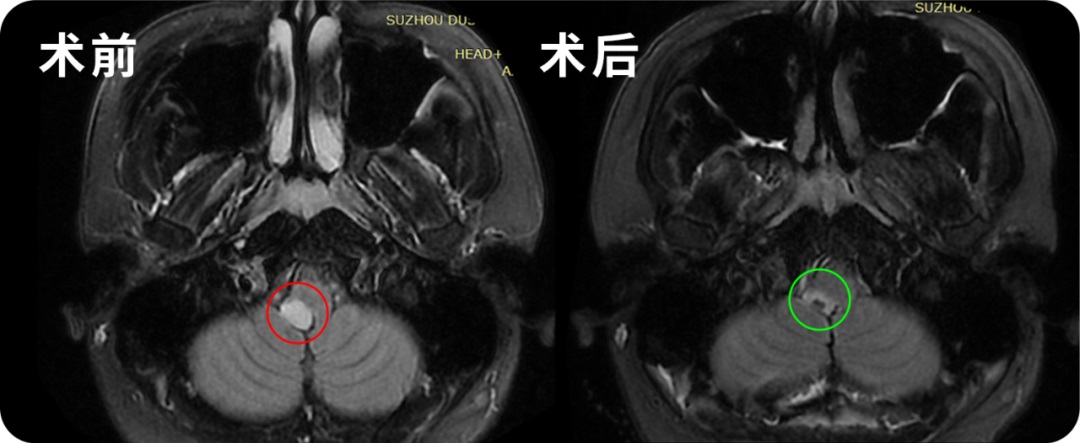

◉治疗过程:2022年11月23日,这台长达12个小时的高难度手术在苏州独墅湖医院顺利完成,手术时长相当于两台手术——延髓和脊随髓内。巴教授全程站立手术,参与了全场手术的国内医生无不惊叹教授无与伦比的手术技术,感叹哪怕在国际范围内,这样大的一个手术也是少见。

◉术后情况:术后一天ICU查房,郑女士意识清楚,呼吸吞咽等功能也正常,也没有出现四肢瘫痪的情况。术后12天查房,郑女士已经可以正常下地站立,肢体活动正常,除了右手稍微无力,教授鼓励她相信自己可以恢复的。

术后3个月,在郑女士传来的康复视频里,她如今已经可以正常行走,术后无力的右手已经也可以正常抓握小物体、手部运动正常。虽然动作还略显笨拙,但是对于曾经不幸罹患脑干-延髓室管膜瘤病变累及范围达15cm,曾被告知手术十有九瘫的她来说,这份笨拙就如一次新生,像孩子重学走路一般,充满着希望和勇气。